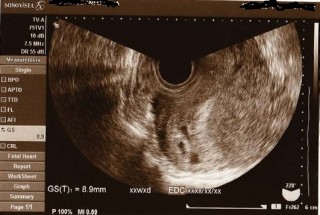

まだ心拍は確認できていない状態です。 胎嚢は8.9mm(真ん中の+‥+で測られているもの)でそのわきに2つほど出血の跡があります。 出血が体外に出てきたらすぐに病院に来るように言われました。 幸い現在6W0Dですが出血はありません。